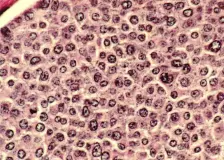

Artemis II: Bezpečně zpátky na Zemi Závěrečná fáze mise Artemis II se během desátého letového dne nesla ve znamení posledních příprav na návrat do zemské atmosféry. Posádka kosmické lodi Orion dokončila konfiguraci kabiny pro vstup, zajistila volně uložené vybavení a provedla finální kontrolu systémů řízení, navigace i komunikace. V této fázi již byla loď na stabilizované návratové dráze po předchozích korekčních manévrech. Príspev… Elektráreň Slapy po takmer roku opäť pracuje naplno, ČEZ dokončil výmenu rýchlouzáveru Vodná elektráreň Slapy opäť dodáva elektrinu do siete celým svojím výkonom.Vodná elektráreň Slapy je po takmer ročnej od... Aprílové číslo NEXTECH už v predaji. Toto sú hlavné témy Ani tentoraz si nenechajte ujsť množstvo zaujímavých článkov zo sveta technológií a taktiež skvelú súťaž o inteligentné hodinky MOTOROLA MOTO WATCH. Tu je výber len zopár z hlavných článkov: BRAINROT: Digitálna hniloba žerie mozog zaživa Rozhovo ... Vedci zistili, že nádory sú „závislé“ od bežného antioxidantu, ktorý si telo vytvára samo. Pomáha im prežiť aj rásť Vedci prišli na zistenie, ktoré mení pohľad na to, ako sa nádory správajú v tele. Ukázali, že rakovinové bunky nevyužívajú len klasické živiny, ... |